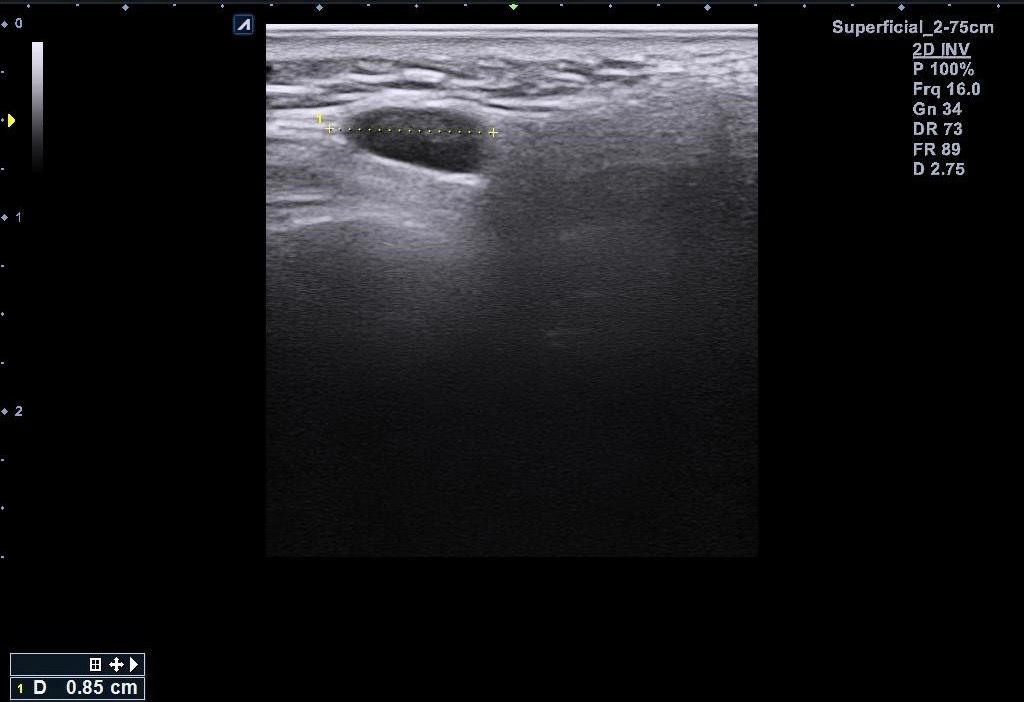

근데 병원에서 지방종이 아니라 임파선 같다고 일단 초음파 본다고 하시고 초음파를 봤는데 의사선생님이 귀 옆에 있는 임파선은 괜찮은데 아래에 있는 임파선이 초음파로 볼때 모양이랑 뭐가 조금 이상하다고 하시면서 대학병원 가보라고 소견서를 써주셨습니다 (소견서랑 초음파사진 첨부할게요)

설명들을때 기억상으로는 1 2번째 초음파사진이 귀 아래였던 거 같아요

• 3번 째 사진

소견서에 따르면, 귀주위 임파선 비대가 있는 환자로서 초음파상 1cm 미만이지만 무증상에 hypervascular하고 귀 밑은 stalk이 잘 안 보인다고 언급되어 있습니다. 크기가 크지 않고 경계가 불규칙하지는 않아 악성의 가능성은 높지 않다고 판단 됩니다. 안내받으신대로 추가검사 및 추적관찰 하시기 바랍니다.